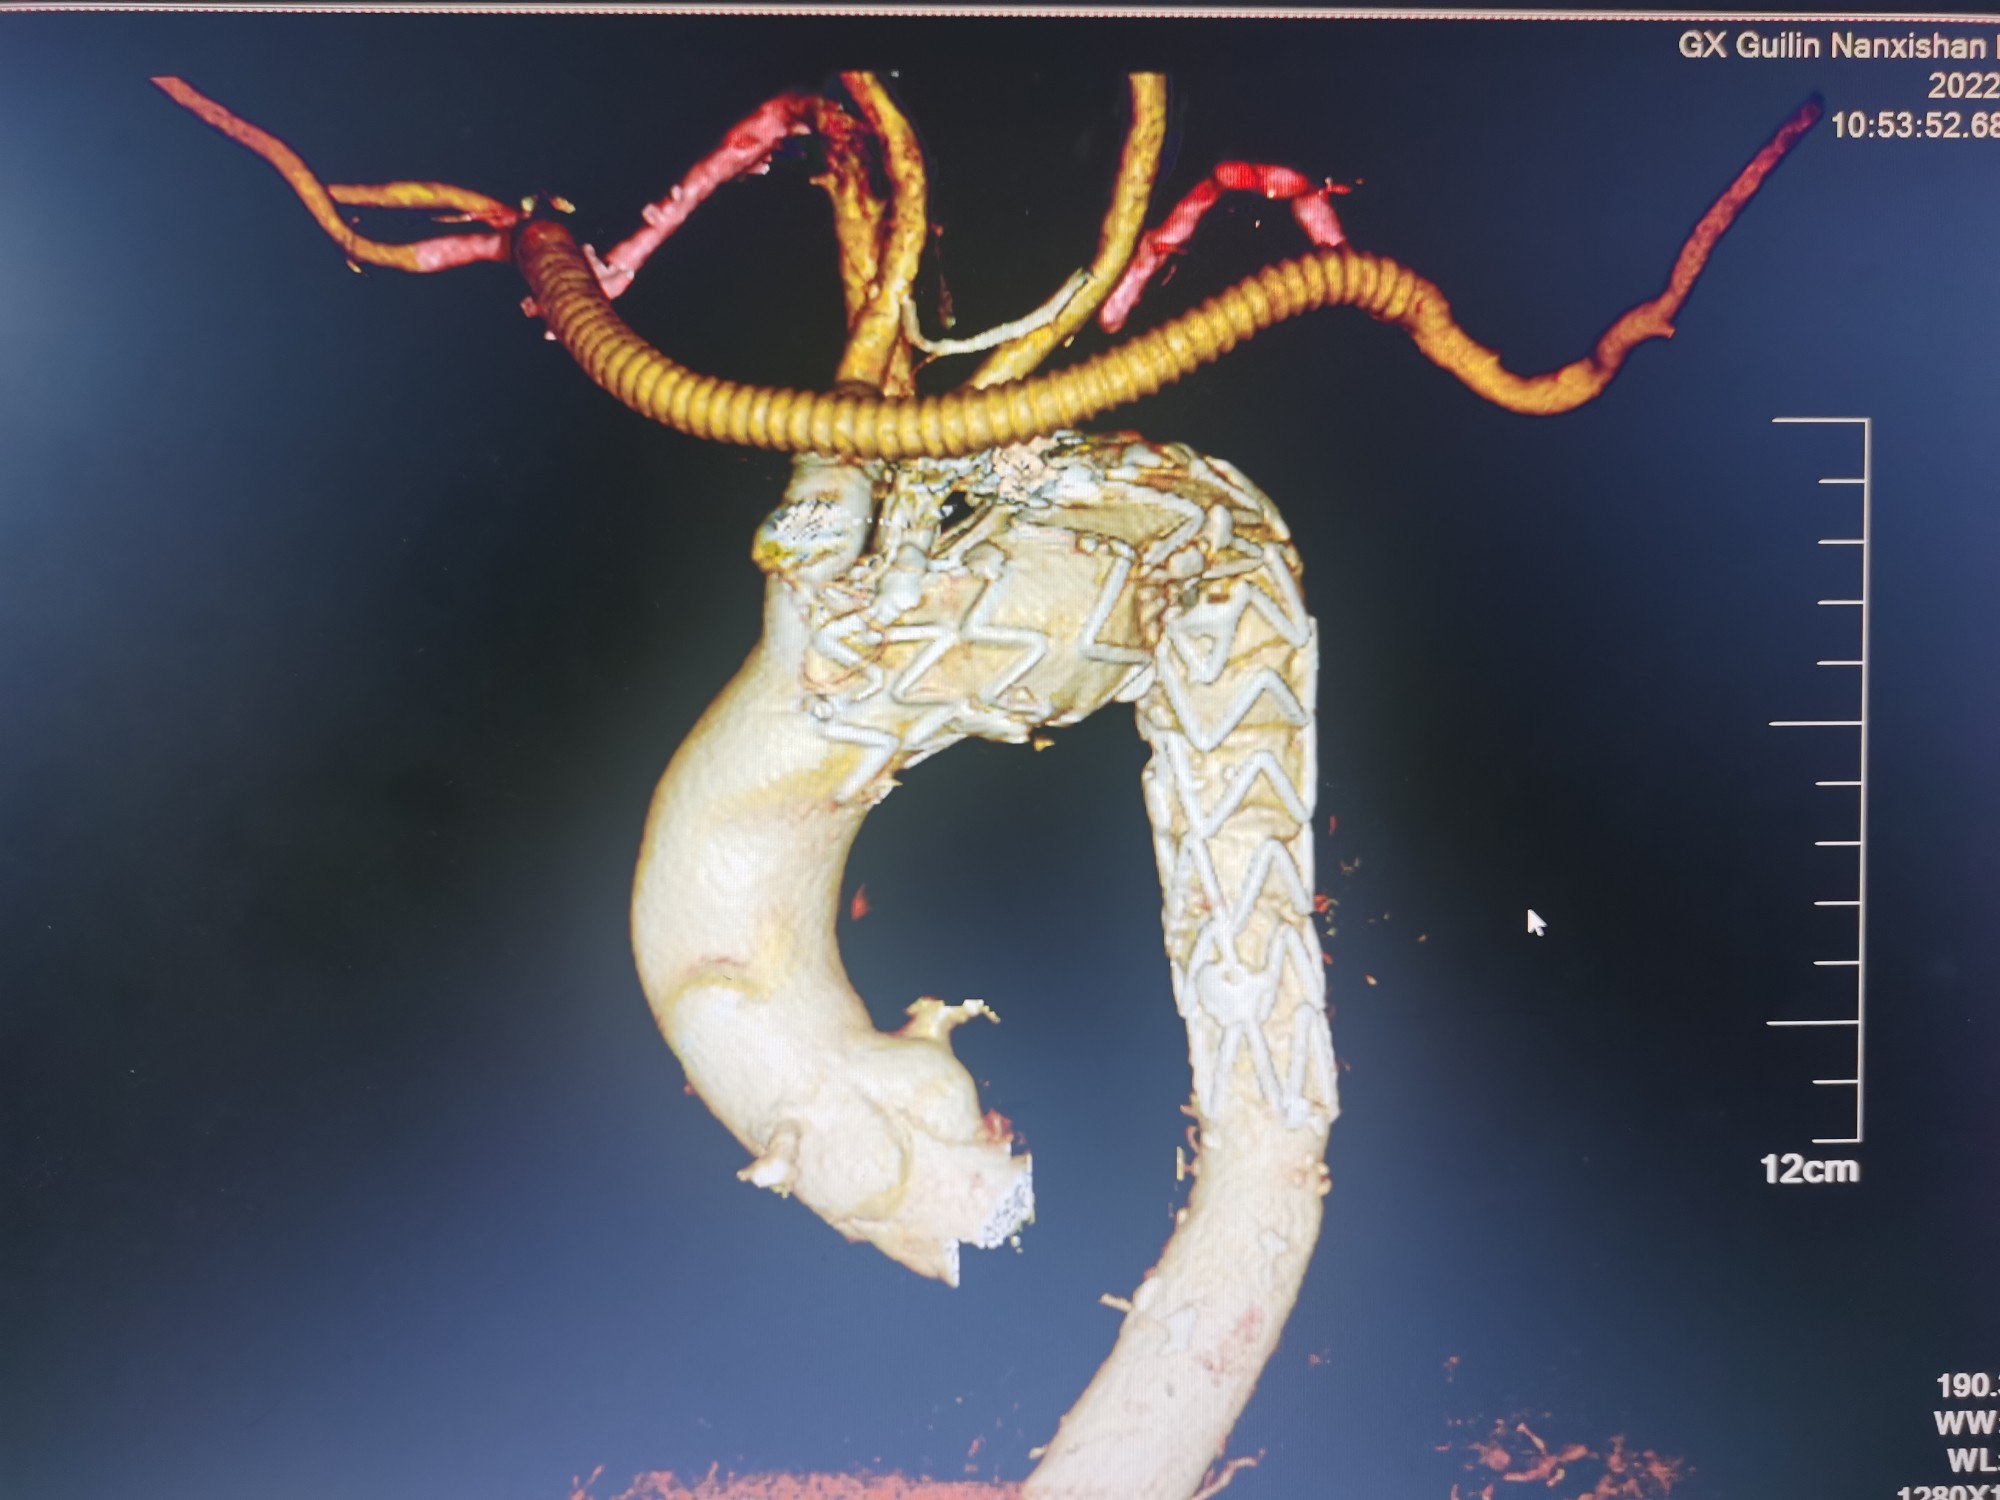

术后CTA三维